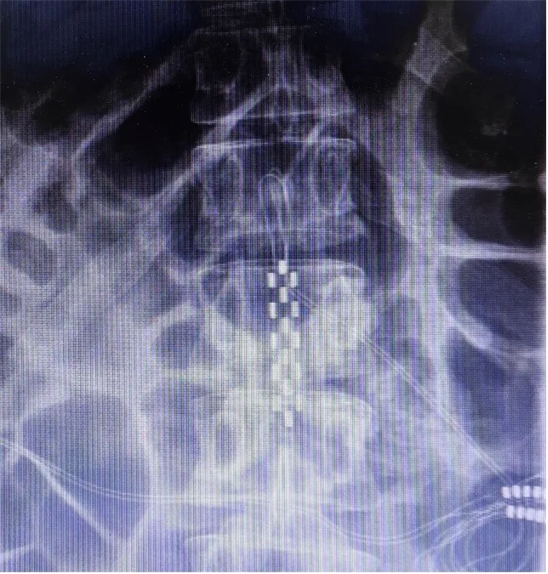

患者長(zhǎng)期以來歷經(jīng)康復(fù)理療及藥物對(duì)癥治療,未見明顯療效,病情仍持續(xù)進(jìn)展,此次專程為尋求脊髓電刺激神經(jīng)調(diào)控治療就診。入院后神經(jīng)調(diào)控專業(yè)組團(tuán)隊(duì)結(jié)合文獻(xiàn)報(bào)道的相關(guān)治療經(jīng)驗(yàn),并經(jīng)過充分的討論,同意實(shí)施脊髓電刺激治療,以改善病人共濟(jì)失調(diào)步態(tài)及平衡障礙。2024年11月20日,夏小雨主任團(tuán)隊(duì)為患者實(shí)施了胸腰段脊髓電刺激電極植入手術(shù)(SCS1期),在術(shù)中影像和術(shù)中電生理的保障下,1根5-6-5觸點(diǎn)電極被準(zhǔn)確植入到T12-L1硬膜外。